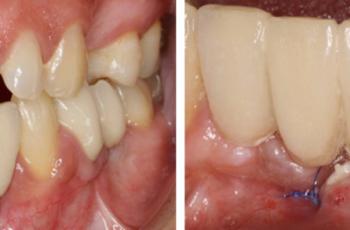

Absceso periodontal Nueva Clasificación Workshop 2017 | UCM Absceso periodontal Casos Clínicos E.T.E.P. – Nueva Clasificación Este proyecto de Casos Clínicos... Periodontitis, estadio IV, grado C Nueva Clasificación Workshop 2017 | UCM Periodontitis, estadio IV, grado C Casos Clínicos E.T.E.P. – Nueva Clasificación Este proyecto de Casos Clínicos... Periodontitis, estadio II, grado A Nueva Clasificación Workshop 2017 | UCM Periodontitis, estadio II, grado A Cátedra Extraordinaria DENTAID en Investigación Periodontal La Cátedra Extraordinaria... Tratamiento no quirúrgico de la periimplantitis. A propósito de un caso... Cirugía periodontal y periimplantaria | UIC Tratamiento no quirúrgico de la periimplantitis. A propósito de un caso... Se presenta el caso de una paciente de 58 años de edad, sin antecedentes médicos de interés y no fumadora. El motivo... Tratamiento de un paciente con periimplantitis Tto. Periimplantario | UCM Tratamiento de un paciente con periimplantitis Presentamos un caso clínico sobre el tratamiento de un paciente con periimplantitis, elaborado... Tratamiento de un paciente con periodontitis crónica I Tto. Periodontal | UCM Tratamiento de un paciente con periodontitis crónica I Presentamos un caso clínico, elaborado por los Doctores Eduardo Montero y David Herrera de la... Efectividad del Tratamiento en Periodontitis Agresiva Tto. Periodontal | UIC Efectividad del Tratamiento en Periodontitis Agresiva El mantenimiento de la dentición natural en estado de salud ha sido un objetivo importante en... Injerto gingival libre alrededor de implantes dentales. A propósito de un... Cirugía periodontal y periimplantaria | UIC Injerto gingival libre alrededor de implantes dentales. A propósito de un... La cirugía mucogingival reconstructiva alrededor de implantes corrige los defectos de la... Injerto de tejido conectivo en el tratamiento de defectos mucosos... Cirugía periodontal y periimplantaria | US Injerto de tejido conectivo en el tratamiento de defectos mucosos... A continuación se presenta un caso clínico de un defecto mucogingival alrededor de un implante...